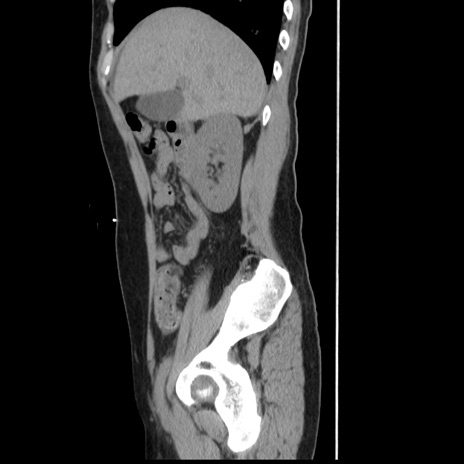

症例10(矢状断像)

【症例】 50歳代女性

【主訴】 腹痛

【現病歴】前日生レバーを食べた。今朝に排便あり。 昼前に突然発症の腹痛を生じ、当院救急外来を受診した。

【既往歴】 子宮筋腫にてで子宮全摘後

【身体所見】 意識清明、腹部:平坦、軟、下腹部やや左を中心に圧痛・反跳痛あり、筋性防御あり

【データ】WBC 7800、CRP 0.07